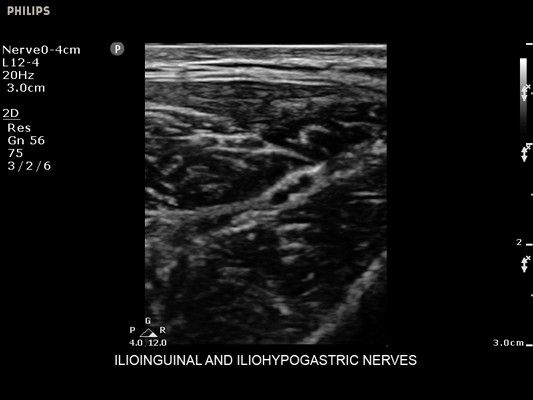

• Диагностика нервов

• Линейный УЗИ датчик Philips L12-4